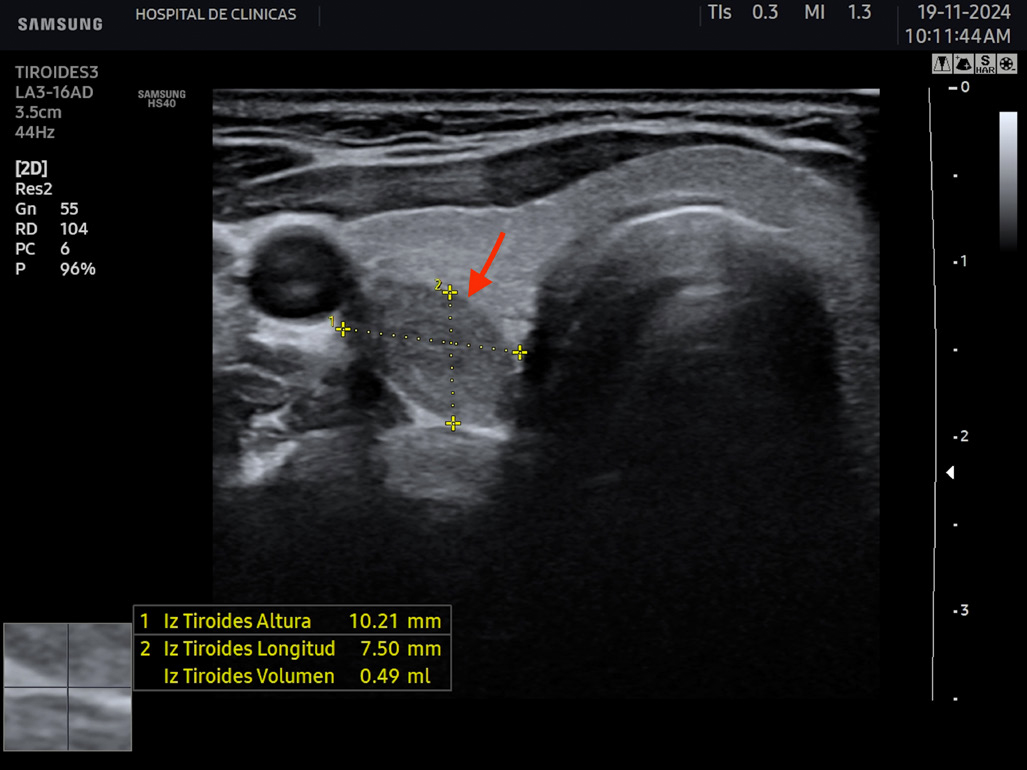

La hipoecogenicidad del parénquima glandular se correlaciona con el grado de infiltración linfocitaria, atrofia de los folículos y disminución del contenido coloide. Esto genera menos reflexión de las ondas sonoras y, por lo tanto, menor ecogenicidad6. Se puede encontrar además aspecto micro o macronodular. Se denominan seudonódulos a las áreas de intensa infiltración linfocitaria local, las cuales deben ser diferenciadas de los nódulos verdaderos que requieren otro seguimiento6. En la figura 6 se aprecian estas características comentadas.

Figura 6: Corte transversal y longitudinal de tiroides de paciente con tiroiditis de Hashimoto. Se señala la disminución de la ecogenicidad, estructura

heterogénea, seudonodular.